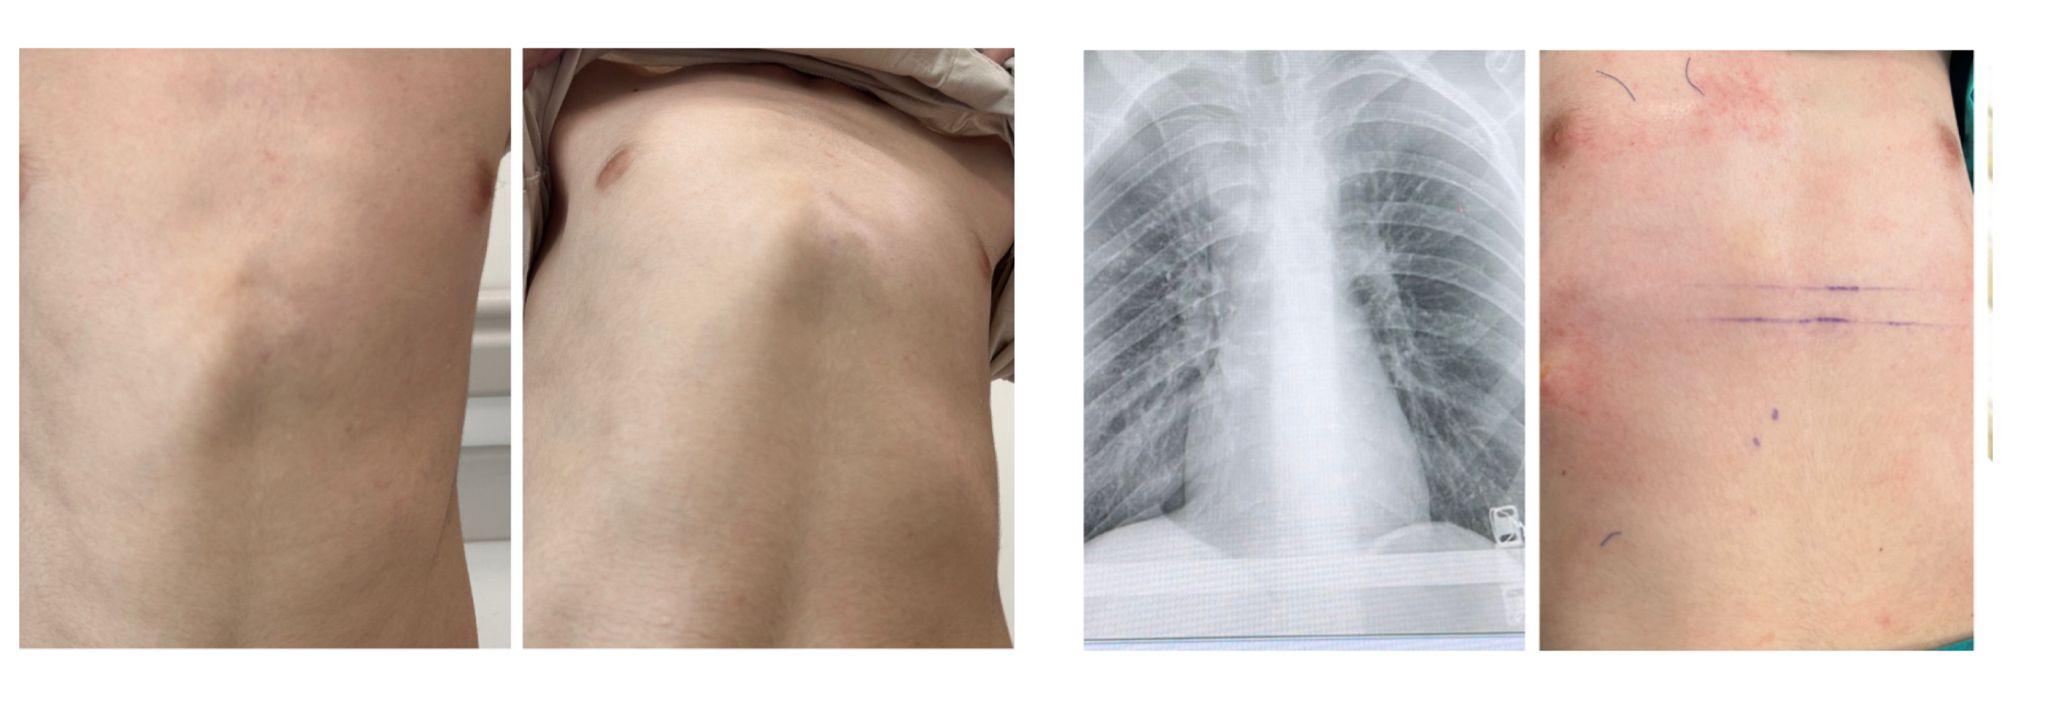

tek bar ile düzeltilmiş kunduracı göğsü filmleriyle

kunduracı göğsünde ameliyat sonrası filminde kalp kenarlanın normale dönmesi